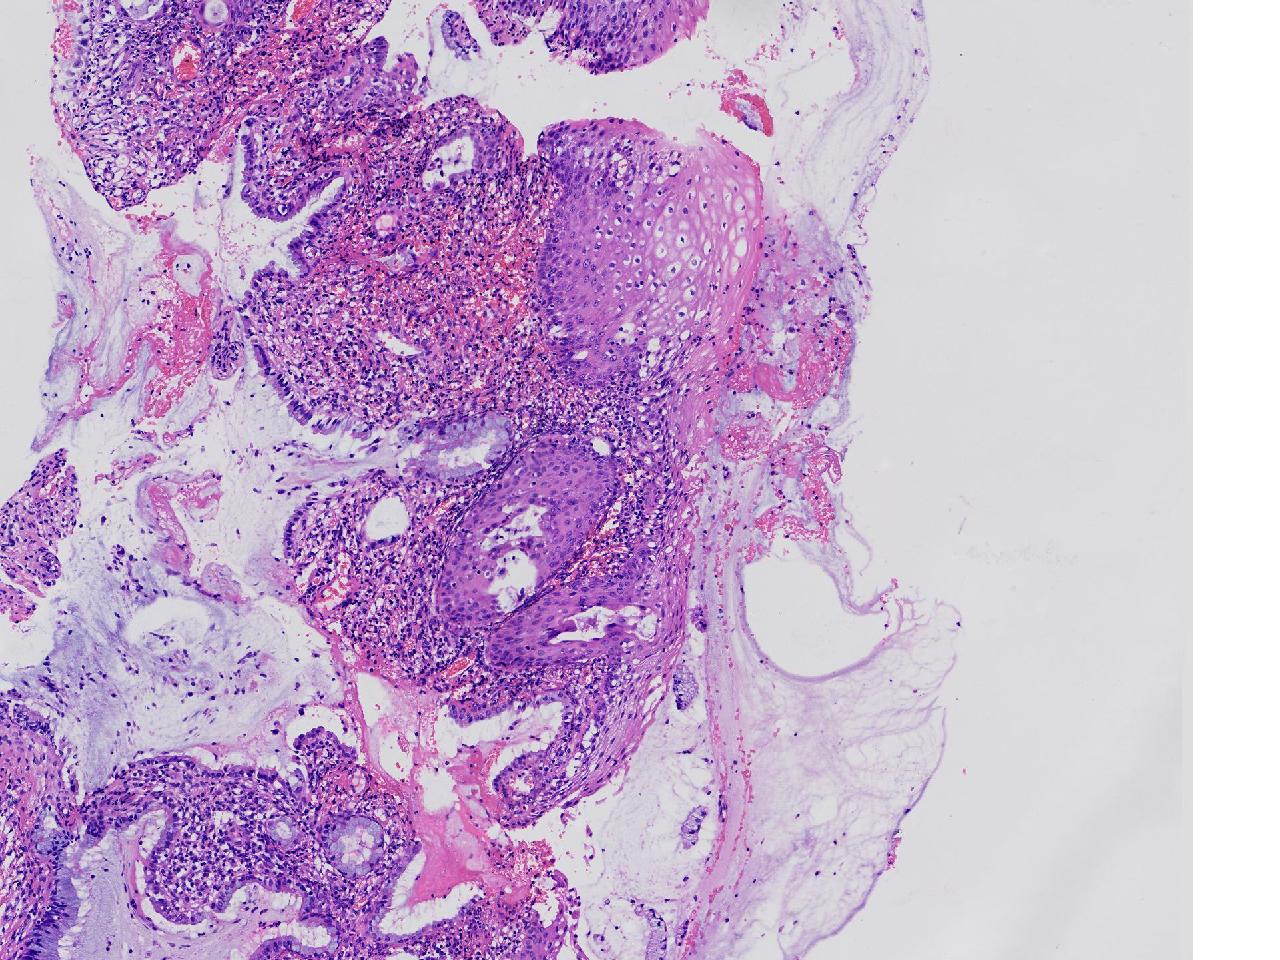

CIN1级? CIN2级?

女,41岁,宫颈活检,HPV16(+)

宫颈多点活检。

灰白色不整形软组织多块。

图3

慢性宫颈炎伴鳞化,建议定期复诊

慢性炎,储备细胞增生伴鳞化,